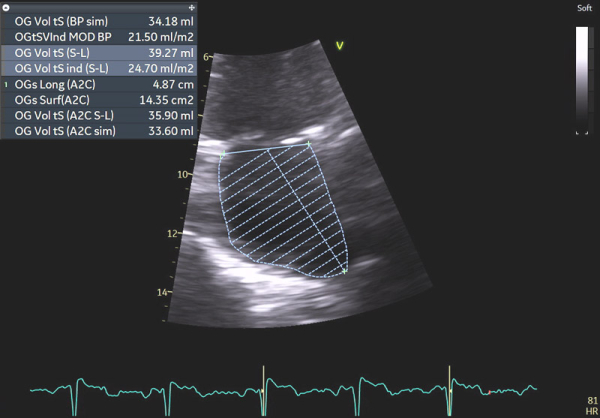

Image 8 : échocardiographie 2D, calcul du volume indexé de l’oreillette gauche (OG)

Image 9 : échocardiographie 2D en incidence sous-costale, mesure de l’épaisseur de la paroi du ventricule droit (VD)

Image 10 : échocardiographie 2D en incidence sous-costale, mesure du diamètre de la veine cave inférieure

En effet, c’était le diagnostic à éliminer en priorité devant les symptômes présentés par la patiente avec un ECG légèrement microvolté et des éléments évocateurs d’une amylose cardiaque à l’échocardiographie : hypertrophie VG très minime mais > 10 mm chez une femme (> 11 mm chez un homme) (cf Vidéo 1 et Image 1), hypertrophie VD à 6 mm (>5 mm) (cf Image 9) et l’altération des strains longitudinaux basaux à l’AFI après valeurs préservées à l’apex (cf Image 7).

En cas d’atteinte précoce d’amylose cardiaque, ce sont en effet les premières anomalies à pouvoir être objectivées et il peut ne pas y avoir encore d’altération marquée du SLG (cf Image 7), de signe de dysfonction diastolique VG (cf Images 3 et 4), de dilatation de l’OG (cf Image 8), de dysfonction systolique du VD (cf Image 5) et les pressions peuvent être normales.